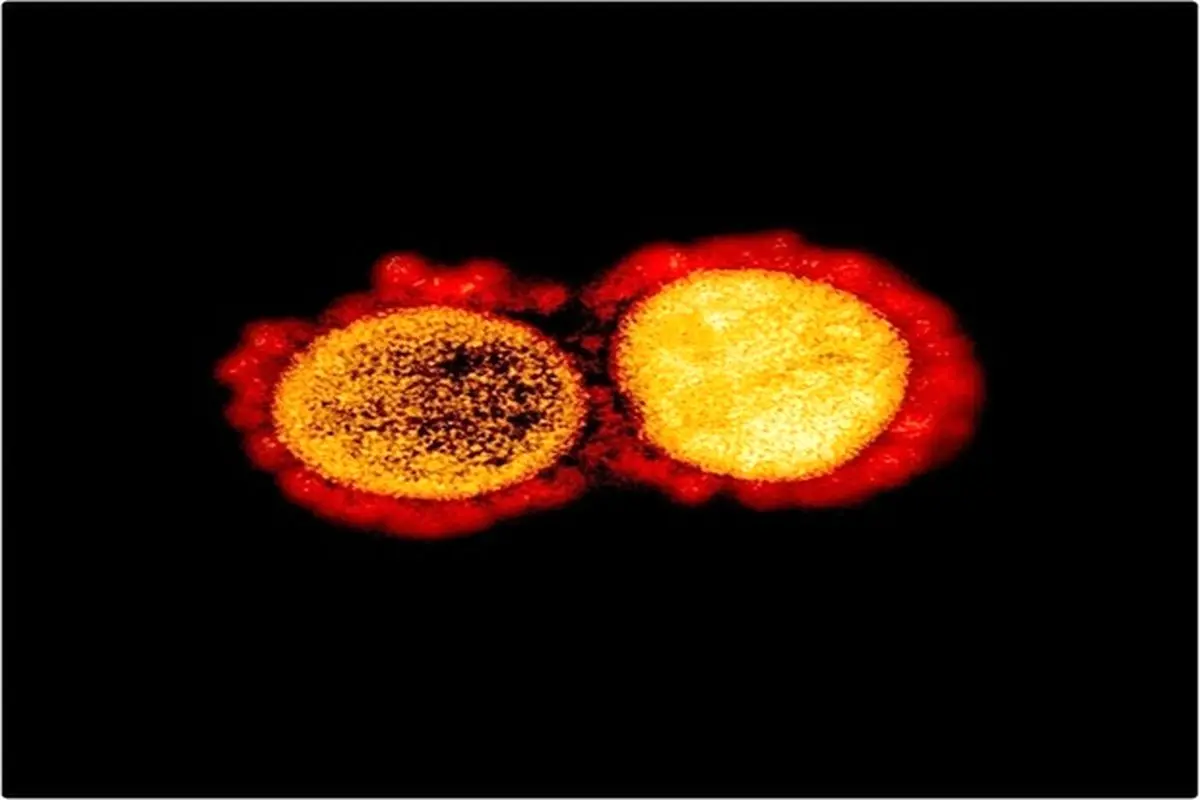

جهان بدون شک با "ویروس X" روبرو خواهد شد

پارسینه: گائو فو، رئیس CDC چین از ظهور ویروس جدید اطمینان دارد و جهان را به تعامل دعوت کرد.

به گزارش اسپوتنیک, گائو فو رئیس مرکز کنترل و پیشگیری از بیماریهای چین، در سخنرانی خود در مجمع بین المللی علم و فناوری در جامعه، اظهار اطمینان کرد که مطمئناً بشریت در آینده با ویروس جدیدی روبرو خواهد شد و اصل تعامل را برای تهیه اقدامات متقابل پیشنهاد کرد.

این متخصص گفت: جهان نه تنها با همه گیری ویروس کرونا بلکه با تعدادی از مشکلات دیگر مانند اینفودمی، هنگامی که اطلاعات مربوطه و اطلاعات غلط در هم آمیخته، روبرو است. این باعث ایجاد شایعات و مشکلات زیادی میشود که باید حل شوند.